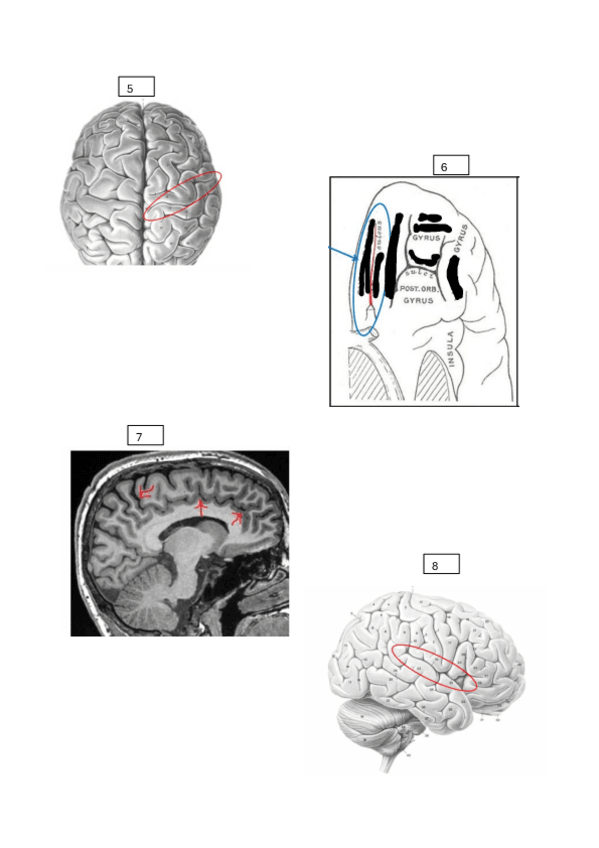

Fotos de las diapositivas desordenadas y sin nombres para practicar los surcos, cisuras y giros que entran en el exámen del primer laboratorio.

13 páginas

Resumen de las áreas de broadman del lab 1, si os portais bien os hago un resumen del resto del lab

4 páginas

Temario para primer control de Lab

7 páginas